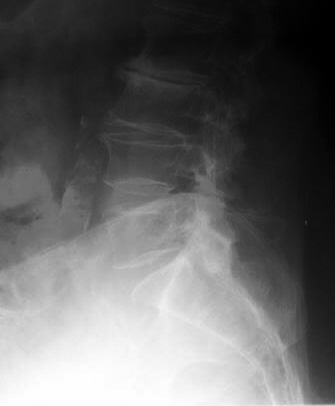

Look at the radiograph below. Where was the fracture?

Click on the picture for the answer.

Lateral view